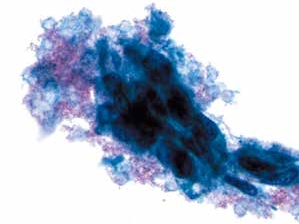

图4-50 角化型鳞癌(高倍、液基、巴氏染色)

肿瘤素质:变性细胞、坏死性碎片及陈旧性出血。此为鳞癌与HSIL的鉴别点之一,浸润性宫颈鳞癌常伴有肿瘤素质。

图4-51 角化型鳞癌(中倍、液基、巴氏染色)

肿瘤素质:坏死性碎片、纤维蛋白及陈旧性出血。HSIL的背景相对干净,鳞癌常伴有肿瘤素质。